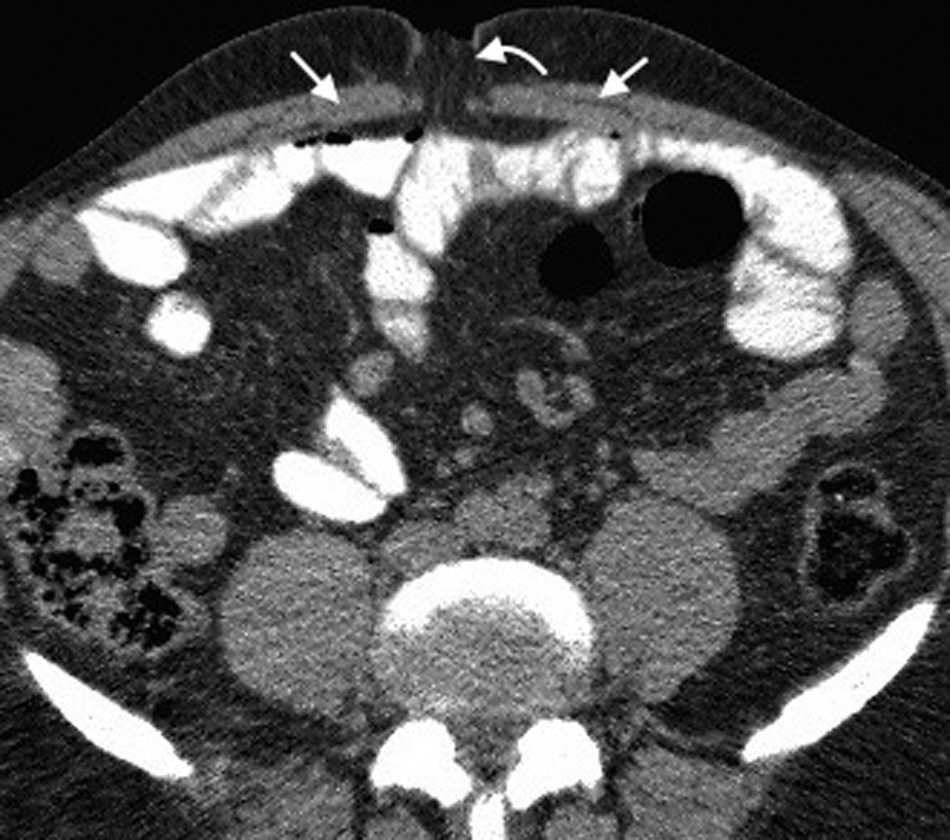

La hernia inguinal indirecta atraviesa el anillo inguinal interno, recorre el conducto y emerge a trav??s del anillo externo, sobresaliendo superior y externamente a los vasos epig??stricos inferiores. Puede extenderse por el conducto esperm??tico o el ligamento redondo hacia el escroto o los labios mayores, respectivamente. Es posible ver el cuello del saco herniario en el anillo inguinal profundo1 (fig. 1). Un hallazgo que ayuda a su caracterizaci??n es el signo del gancho. Este debe su nombre a la forma c??ncava que adopta la arteria epig??strica inferior en el plano axial en su curso proximal, al ser comprimida por una hernia indirecta6.

En lo que respecta a la directa, esta se ubica por encima del ligamento inguinal y medial a los vasos epig??stricos inferiores, y en general es adquirida. Su incidencia aumenta con la edad por el debilitamiento de la fascia transversal en el tri??ngulo Hesselbach1. Suele ser m??s frecuente en hombres y est?? menos asociada a la estrangulaci??n de las asas, posiblemente porque en general no atraviesa todo el curso del canal4 (fig. 2). El contenido del canal inguinal es comprimido lateralmente, mientras que su grasa se ubica como una luna creciente, produciendo el signo de la semiluna creciente (un hallazgo que ayuda a la caracterizaci??n de estas hernias)7.